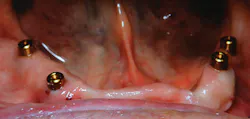

At one month, ISQ readings were taken of all the implants except No. 3. The lower arch showed the soft tissue healing at that time (figure 9). At 2.5 months, readings were taken again, and it was indicated that the mandibular arch had integrated and was ready for final attachment via locator attachments (Zest; figures 10 and 11). The maxillary implants were continuing to show progress, but not to the point where predictable loading was possible. Because the maxillary denture was stable (as most are), this was not an issue. The patient greatly appreciated the completion of the mandibular overdenture, which was very mobile and bothersome.

Figure 10: Locator abutments placed